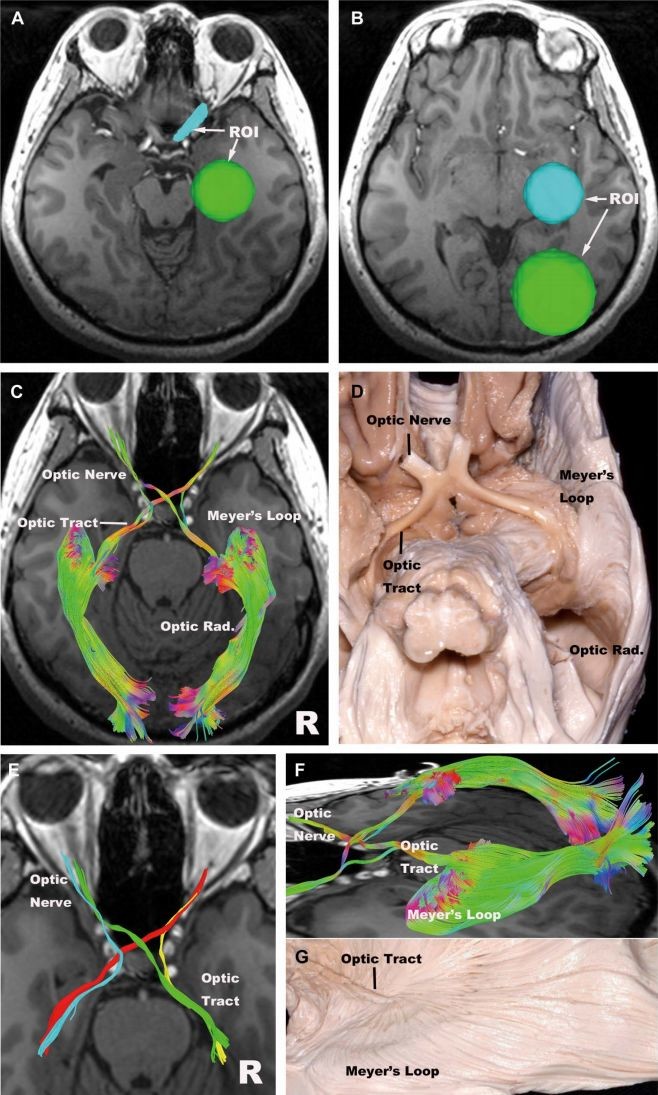

大脑联络纤维束,大脑内部白质纤维束

【收藏】大脑白质解剖

基于约束球面反卷积扩散磁共振的脑白质解剖图谱 - 知乎

实用解剖脑白质纤维束解剖学习对年轻医生手术训练的启示

神外专题二大脑白质纤维束的解剖意义

神外专题(二)| 大脑白质纤维束的解剖意义